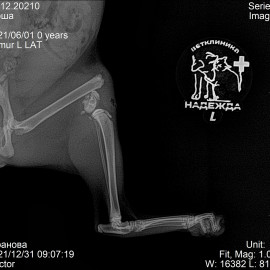

После полученной травмы от удара, кошка перестала вставать на заднюю левую лапу. После осмотра и рентгенологического исследования был поставлен диагноз: перелом левого бедра. 31.12.2021 была проведена операция: остеосинтез левого бедра.

Снимки 2-3 после операции.